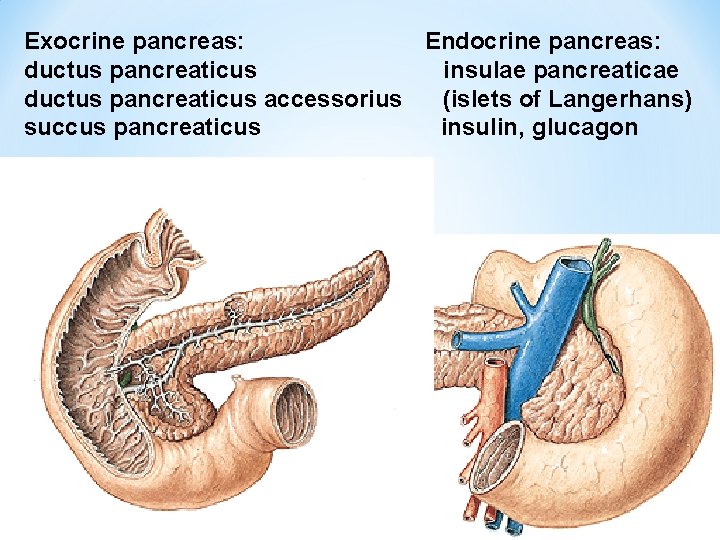

PANCREAS Caput, corpus, cauda, incisura pancreatis, processus uncinatus (a. et v. mesenterica sup. )

Exocrine pancreas: Endocrine pancreas: ductus pancreaticus insulae pancreaticae ductus pancreaticus accessorius (islets of Langerhans) succus pancreaticus insulin, glucagon